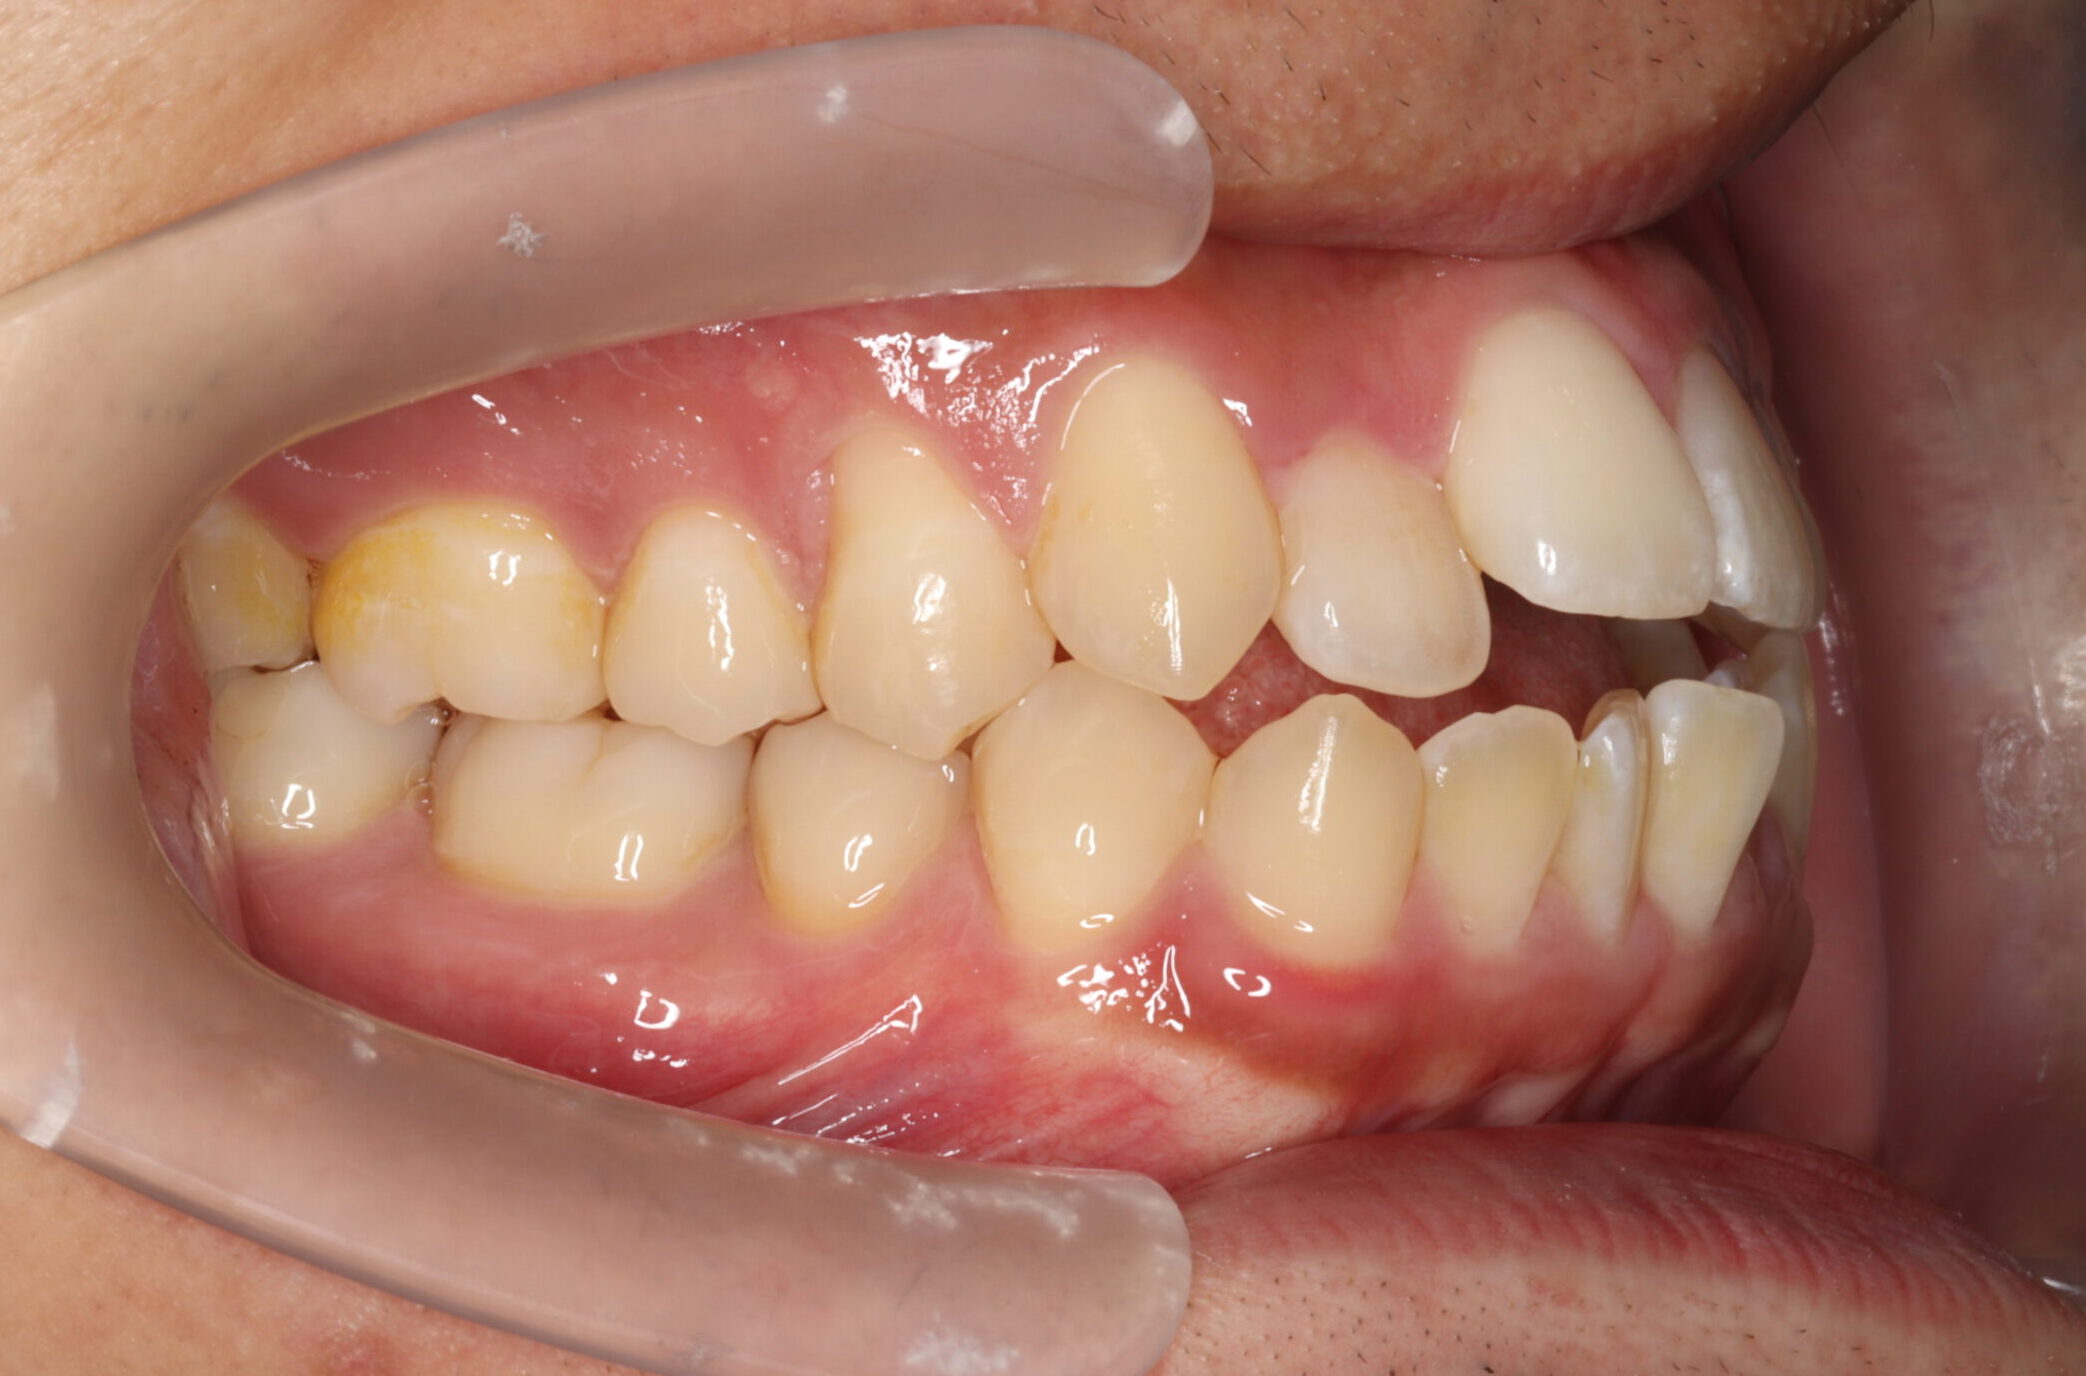

24歳男性 1年11ヵ月

24歳 男性

【主訴】でこぼこ、上下の歯が噛まない

【診断】開咬、叢生(でこぼこ)、上下顎前歯唇側傾斜、舌突出癖

【治療方法】マルチブラケット装置にて排列を行う。咬合の確立のため顎間ゴムを併用し、舌突出癖の改善のため筋機能療法を行う